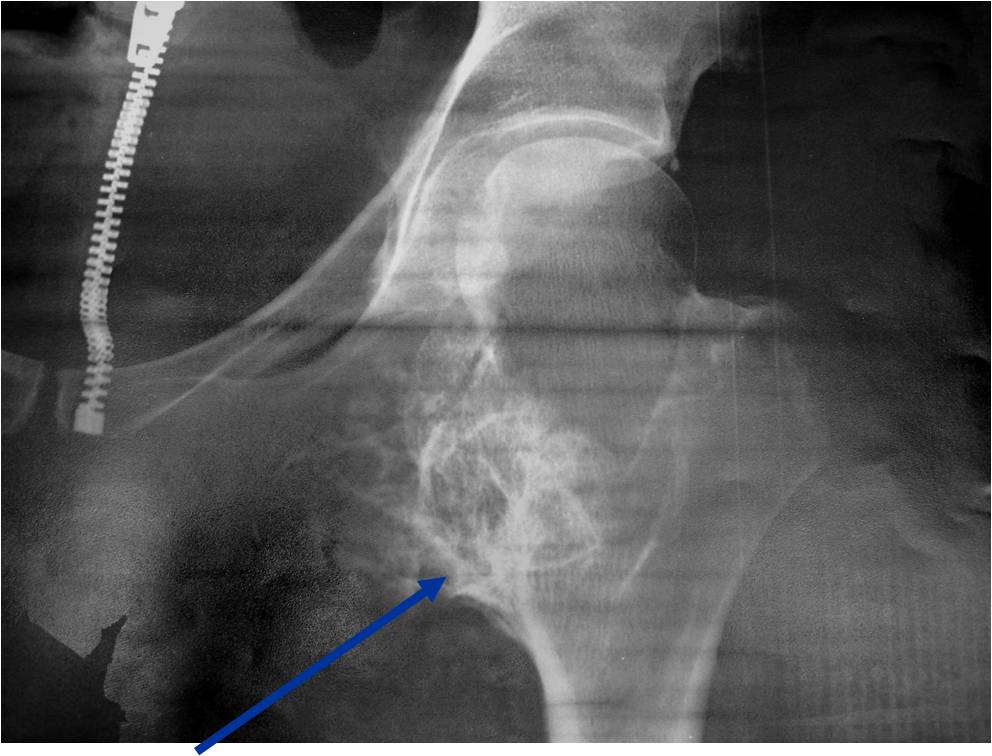

Plain X-ray: Secondary Chondrosarcoma of Proximal Femur

Plain X-rays:

- Projects from bone with narrow (pedunculated) to broad (sessile) stalk

- Corticomedullary continuity: Medullary bone continuous with that of osteochondroma and cortex blends with that of osteochondroma

- Calcification in cartilaginous cap (“Ring and Arc” and stippled calcifications)

- Lobular growth pattern